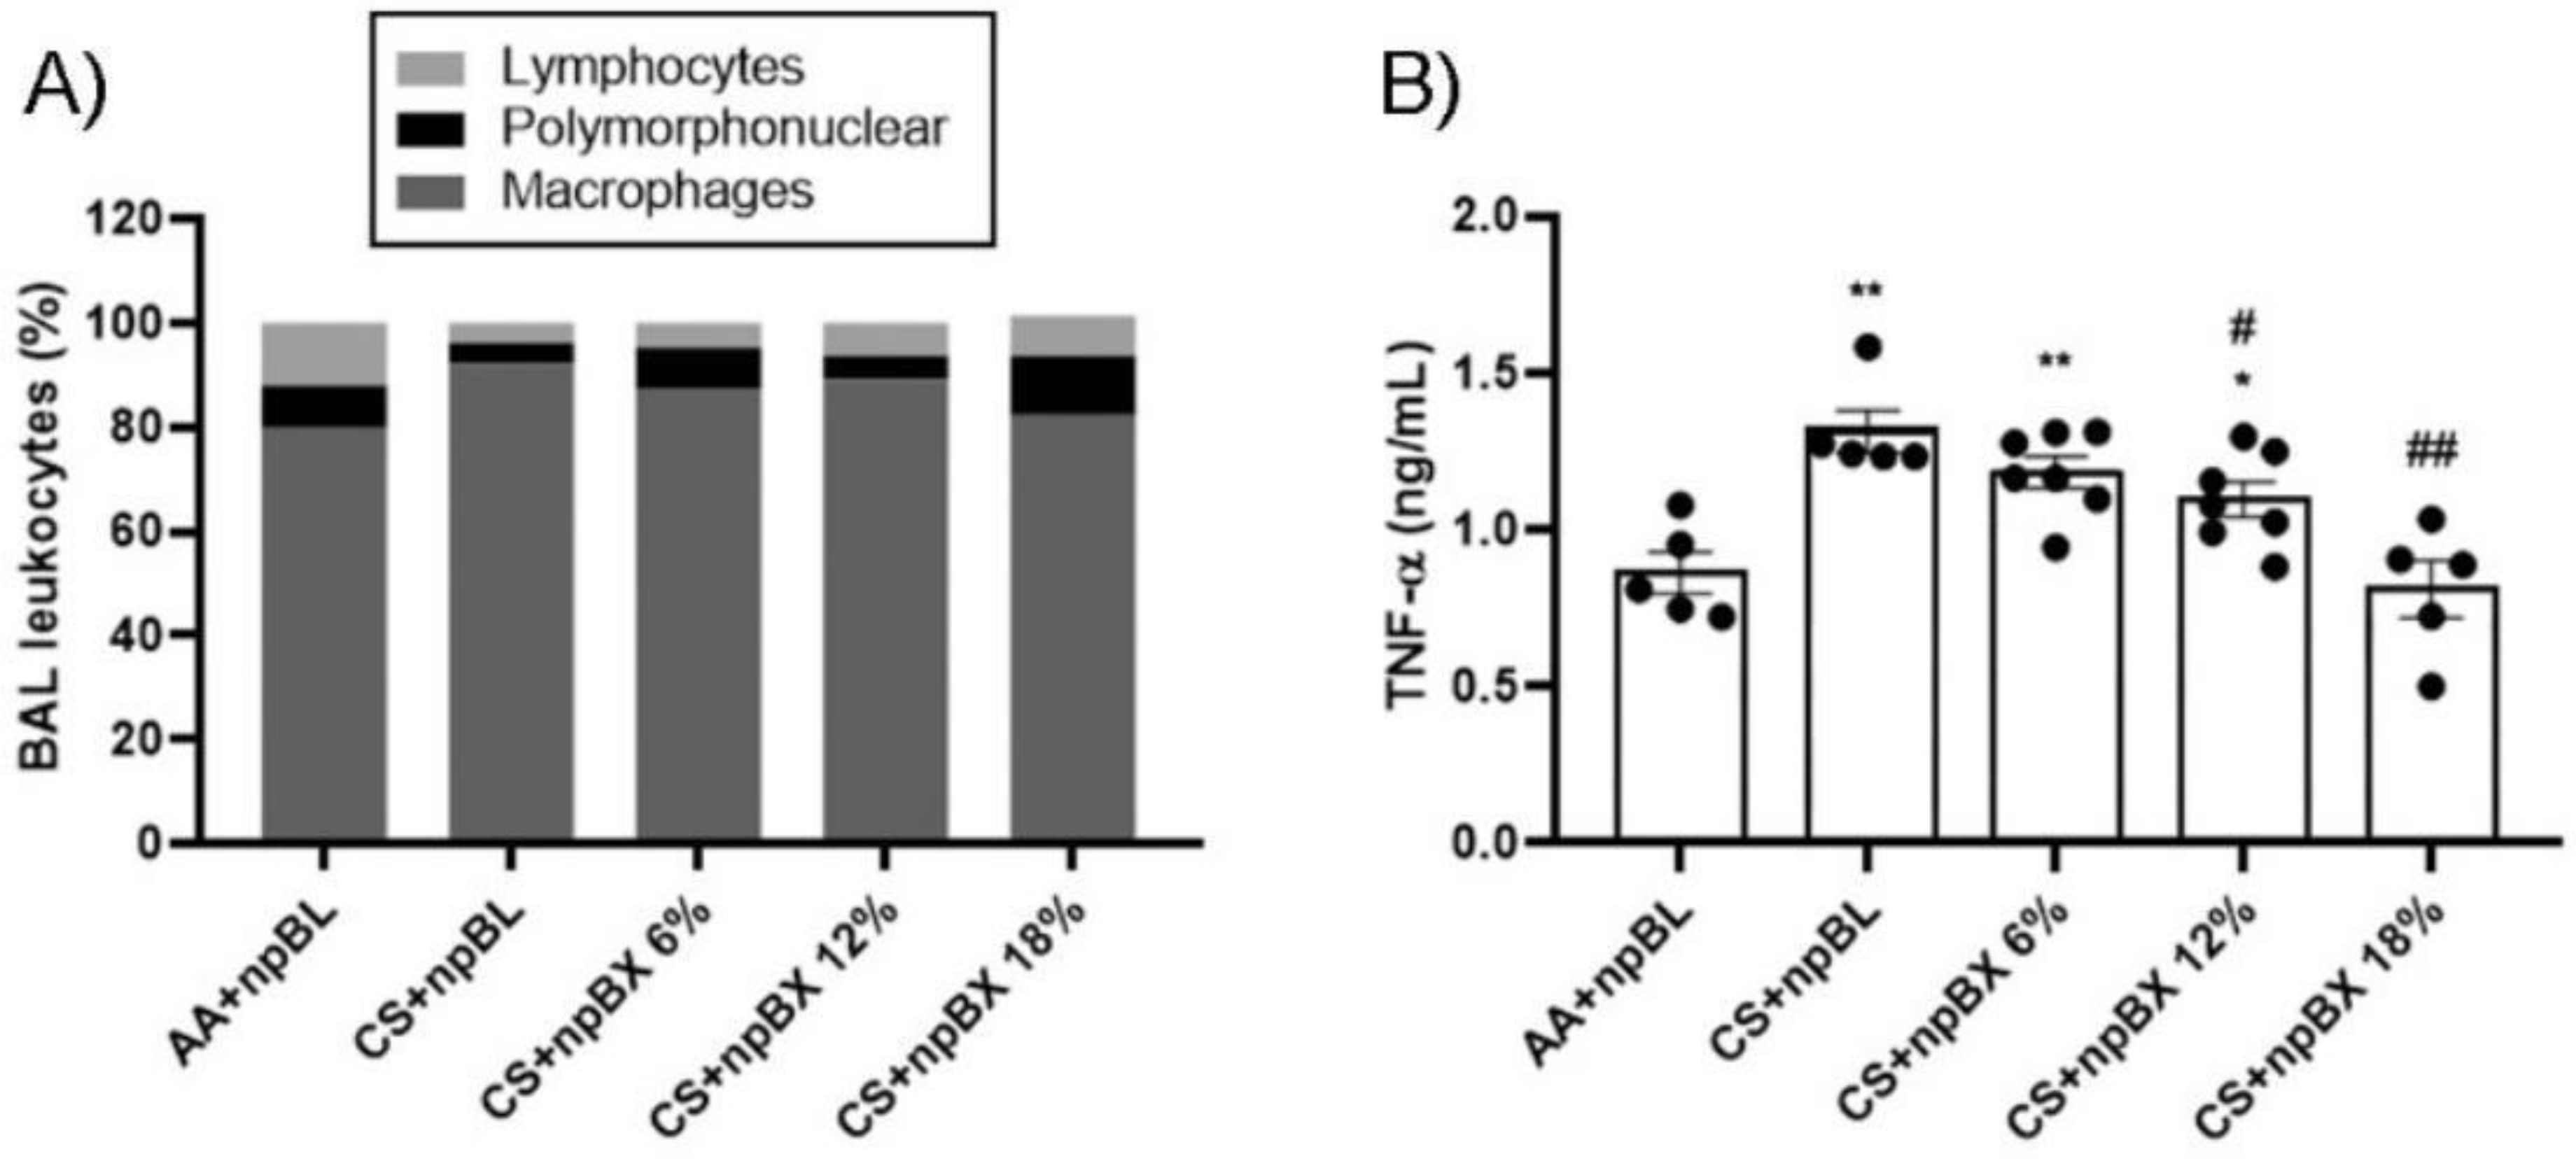

3.3.2. npBX Prevents the Increase in Leukocyte Numbers and TNF-α Levels in BALF from Mice Exposed to CS

| Group | Cell × 105 Mean ± SEM (%) | |||

|---|---|---|---|---|

| Total | Macrophages | Neutrophils | Lymphocyte | |

| AA + npBL | 3.08 ± 0.47 (100) | 2.51 ± 0.35 (79.78) | 0.23 ± 0.06 (8.11) | 0.34 ± 0.06 (12.11) |

| CS + npBL | 6.24 ± 0.88 (100) *** | 5.77 ± 0.80 (92.15) *** | 0.26 ± 0.05 (4.14) | 0.21 ± 0.03 (3.71) * |

| CS + npBX 6% | 4.94 ± 0.9 (100) * | 4.36 ± 0.76 (87.5) *** | 0.37 ± 0.09 (7.83) | 0.21 ± 0.05 (4.67) * |

| CS + npBX 12% | 3.84 ± 0.53 (100) ## | 3.44 ± 0.45 (89.19) ### $$ | 0.17 ± 0.04 (4.56) $ | 0.23 ± 0.04 (6.27) |

| CS + npBX 18% | 3.26 ± 0.7 (100) ### $ | 2.64 ± 0.48 (82.19) ### $$$ | 0.36 ± 0.15 (11.66) | 0.26 ± 0.07 (7.6) |